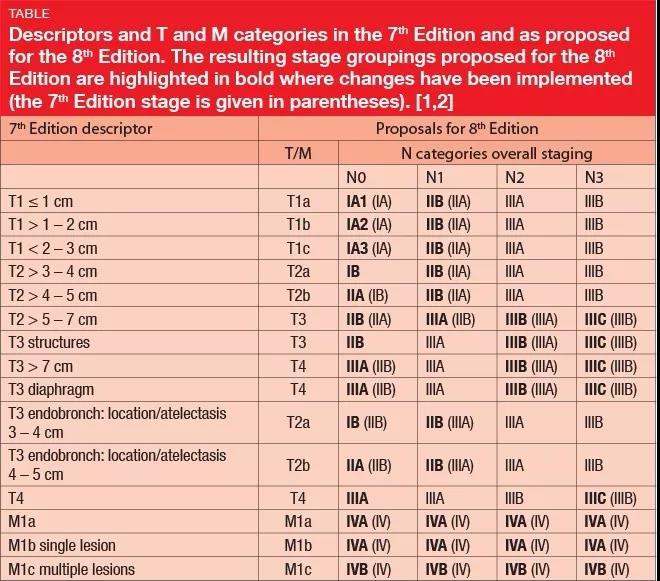

那么问题来了,目前好像没有强调STAS肿瘤侵袭扩散对现在的肺癌临床和病理分期标准有什么影响。世界卫生组织明确表示,STAS是肺癌侵袭扩散的一种形式,在TNM分期中,似乎STAS应该属于远处转移M的范畴,按照远处转移的定义,STAS套不上M1a, M1b和M1c。STAS肯定无法和N有任何关联,那么和T有关联,T只跟肿瘤大小、生长方式和细胞类型有关系。世界卫生组织明确规定,计算肿瘤大小,不能包含STAS侵袭扩散的范围。有了STAS肿瘤侵袭扩散,那么小于3.0厘米的肺癌,还能定义为T1a, T1b和T1c吗?STAS肿瘤侵袭扩散,会提高术后复发率和降低总体生存率,在手术前评估和制定手术切除范围时,能算作一个预测因素,但是在肺癌临床分期上STAS算个什么东西呢?

以上表格为第七版和第八版肺癌TNM分期标准的比较

因收集病例比较久远,故作者采用第七版TNM肺癌分期标准。下面,我们看看Gouji Toyokawa的研究结果: